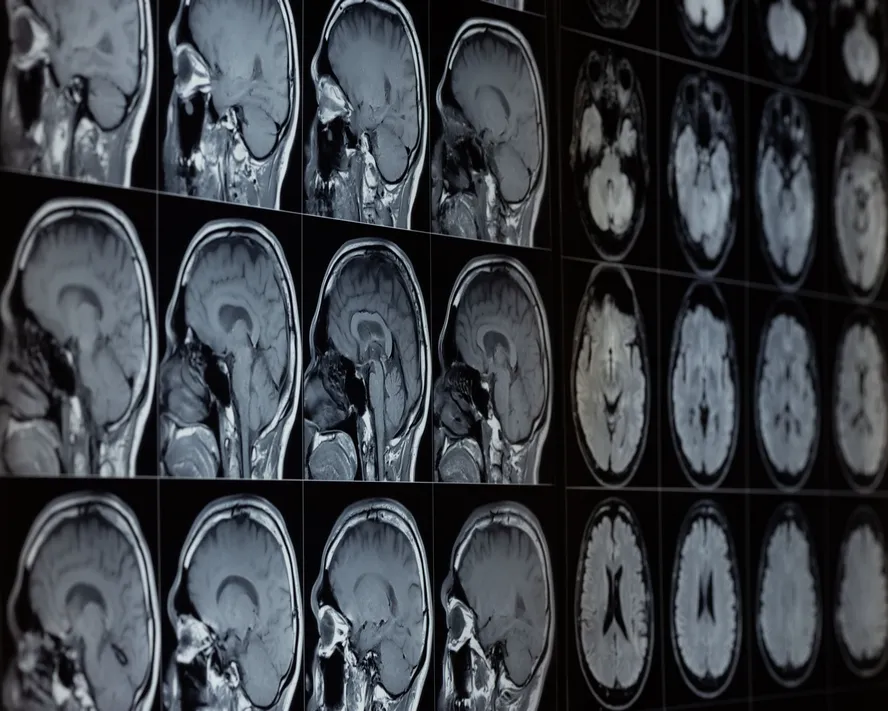

Alzheimer Nedir? Alzheimer Belirtileri ve Tedavisi

Halk arasında bunama olarak da bilinen demans hastalığının en yaygın formu olan Alzheimer, beyin hücrelerinin ölmesine bağlı olarak kişinin bilişsel fonksiyonlarının azalmasına neden olan nörolojik bir hastalıktır.

Alzheimer hastalarının hekime başvurması çoğunlukla ailenin ısrarıyla olur. Hekim, öncelikle kişinin kendisinden ve gerektiğinde ailesinden hastanın öyküsünü dinler. Ardından nörolojik muayene ile kişinin denge, duyu ve davranışları ölçülür. Kişinin hafızasının mevcut durumunun anlaşılması için bir takım nörolojik hafıza testleri yapılır. Hekim, gerekli gördüğünde radyoloji ve laboratuvar testleri gibi ek tetkikler isteyebilir. Manyetik rezonans (MR), bilgisayarlı tomografi (BT), pozitron emisyon tomografisi (PET) gibi görüntüleme işlemlerinin ardından hekim hastayı değerlendirir. Tüm veriler ışığında kişiye Alzheimer tanısı koyulur.